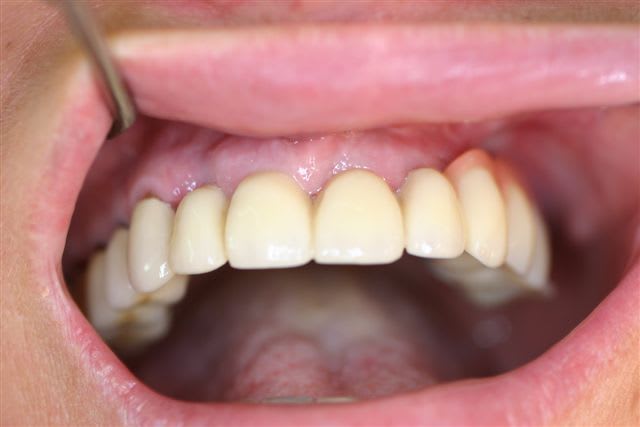

Perte d un greffon iliaque

Retraité en basale voici 6 ans avec succès